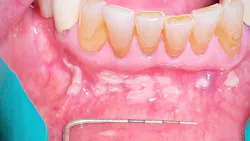

Take a look at the initial photograph. What’s the first thing that comes to your mind? Scattered, white, creamy patches in the lower anterior vestibule, each measuring approx. 3–6 mm (figure 1). Now, take a look at the second picture after the white patches were easily wiped off with gauze (figure 2). Note the red, thin membraned tissue? It was very tender to the touch.This diagnosis should be a slam dunk by now. Yup, you guessed it. Good ol’ pseudomembranous candidiasis, aka thrush.

- Acute pseudomembranous candidiasis consists of creamy, loose patches of desquamative epithelium that are easily removed.1 Red tissue tender to the touch is what is painful to the patient.